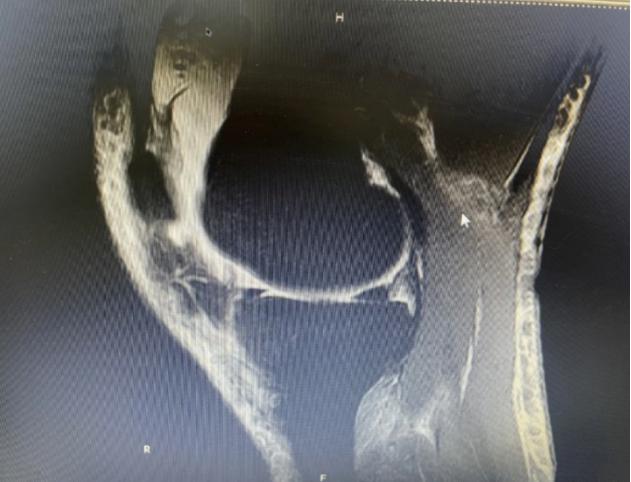

膝关节(双侧)平扫检查结果提示:(1)双膝关节轻度退变,内、外侧半月板后角Ⅱ °损伤。(2)左膝前交叉韧带轻度损伤。(3)双膝关节腔及髌上囊积液。

经PRP治疗1年后,患者因扭伤再次就诊,进行膝关节(双侧)平扫检查,结果提示:(1)双膝关节轻度骨质增生。(2)内、外侧半月板后角退变。(3)左膝前交叉韧带信号增高,炎症反应或损伤待除外。(4)双膝关节腔及关节周围软组织水肿。(5)双侧关节腔及髌上囊少量积液。通过检查结果,可以看出患者经PRP治疗后内、外侧半月板后角损伤有明显好转,从Ⅱ°损伤降至Ⅰ°损伤,且双膝关节腔及髌上囊积液减少。